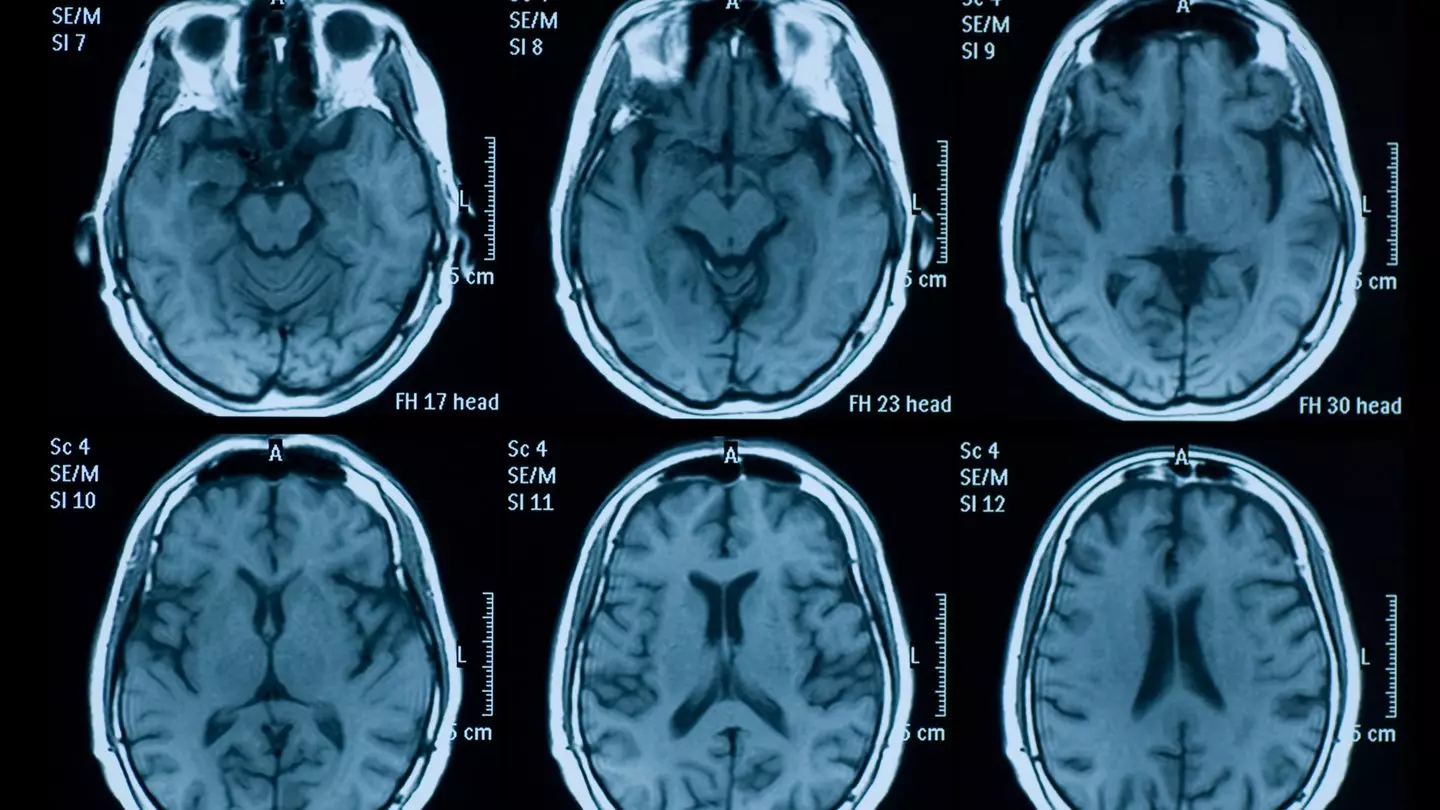

New findings from New York University Langone Health appear to suggest that changes in the brain caused by long COVID may lead to long-term fatigue, brain fog, dizziness, loss of smell or taste, depression and other symptoms.

Senior study author Dr Yulin Ge, a professor in the Department of Radiology at NYU Grossman School of Medicine, explained in an NYU Langone statement: "Our work suggests that long-term immune reactions caused in some cases after an initial COVID infection may come with swelling that damages a critical brain barrier in the choroid plexus."

The National Institutes of Health explains that the choroid plexus is a collection of blood vessels in the ventricles of the brain that produce cerebrospinal fluid and act as a barrier.

A study recently published in the journal Alzheimer’s & Dementia looked at 86 long Covid patients with neurological symptoms, comparing them to 67 people who fully recovered from Covid and 26 healthy people who were never infected.

The researchers discovered that those struggling with long Covid had a choroid plexus that was 10 percent larger than those who recovered quickly.

This was a pretty important discovery because a swollen choroid plexus is a sign of long-term brain inflammation and wear-and-tear, and is linked to the same biomarkers found in people developing Alzheimer’s.

In fact, Dr Ge, one of the researchers, pointed out that this physical change could be an 'early warning sign' of future cognitive decline.

The study also found that patients with this larger brain structure scored about 2 percent lower on a standard 30-point memory and thinking test.

The researchers believe that long Covid might be causing ongoing inflammation that actually thickens the blood vessels in this part of the brain, potentially leading to these long-term symptoms.